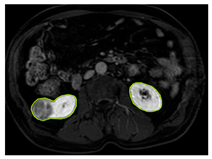

3.2.1. ROI Dataset

The images used in the study include different anatomical areas, such as the liver, spleen, and intestine. However, in order to process the data more quickly and provide more accurate results from the analysis, only the kidney areas (Regions of Interest, ROI) were extracted and evaluated. The Roboflow platform was used for spatial matching and segmentation of the kidneys. Polygonal ROI regions were defined by applying the semantic segmentation method, and then the transformations performed were verified by the radiologist, increasing the reliability of the system. In our study, MRI phase images were acquired at a resolution of 512 × 512 and the renal region of interest (ROI) was segmented and resized to 224 × 224 for input into the DenseNet architecture. In a similar study, Alhussaini et al. utilized 512 × 512 CT images and processed tumor-containing ROIs for their analysis; however, segmented region details were not provided [23]. Another study aimed to differentiate ccRCC from oncocytoma by extracting ROIs from T2-weighted images (T2-WI), pre-contrast T1-weighted images (T1-WI), and post-contrast arterial and venous phases. Tumor regions segmented at 100 × 100 mm were subsequently resized for input into the AlexNet model [24]. Unlike these studies, our approach involves segmenting the entire kidney, rather than solely the tumor region, to enable the deep learning model to leverage structural information for the organ as a whole.

Table 2 shows sample images containing ROI areas for different phases.

Table 2.

ROI areas in different phases.